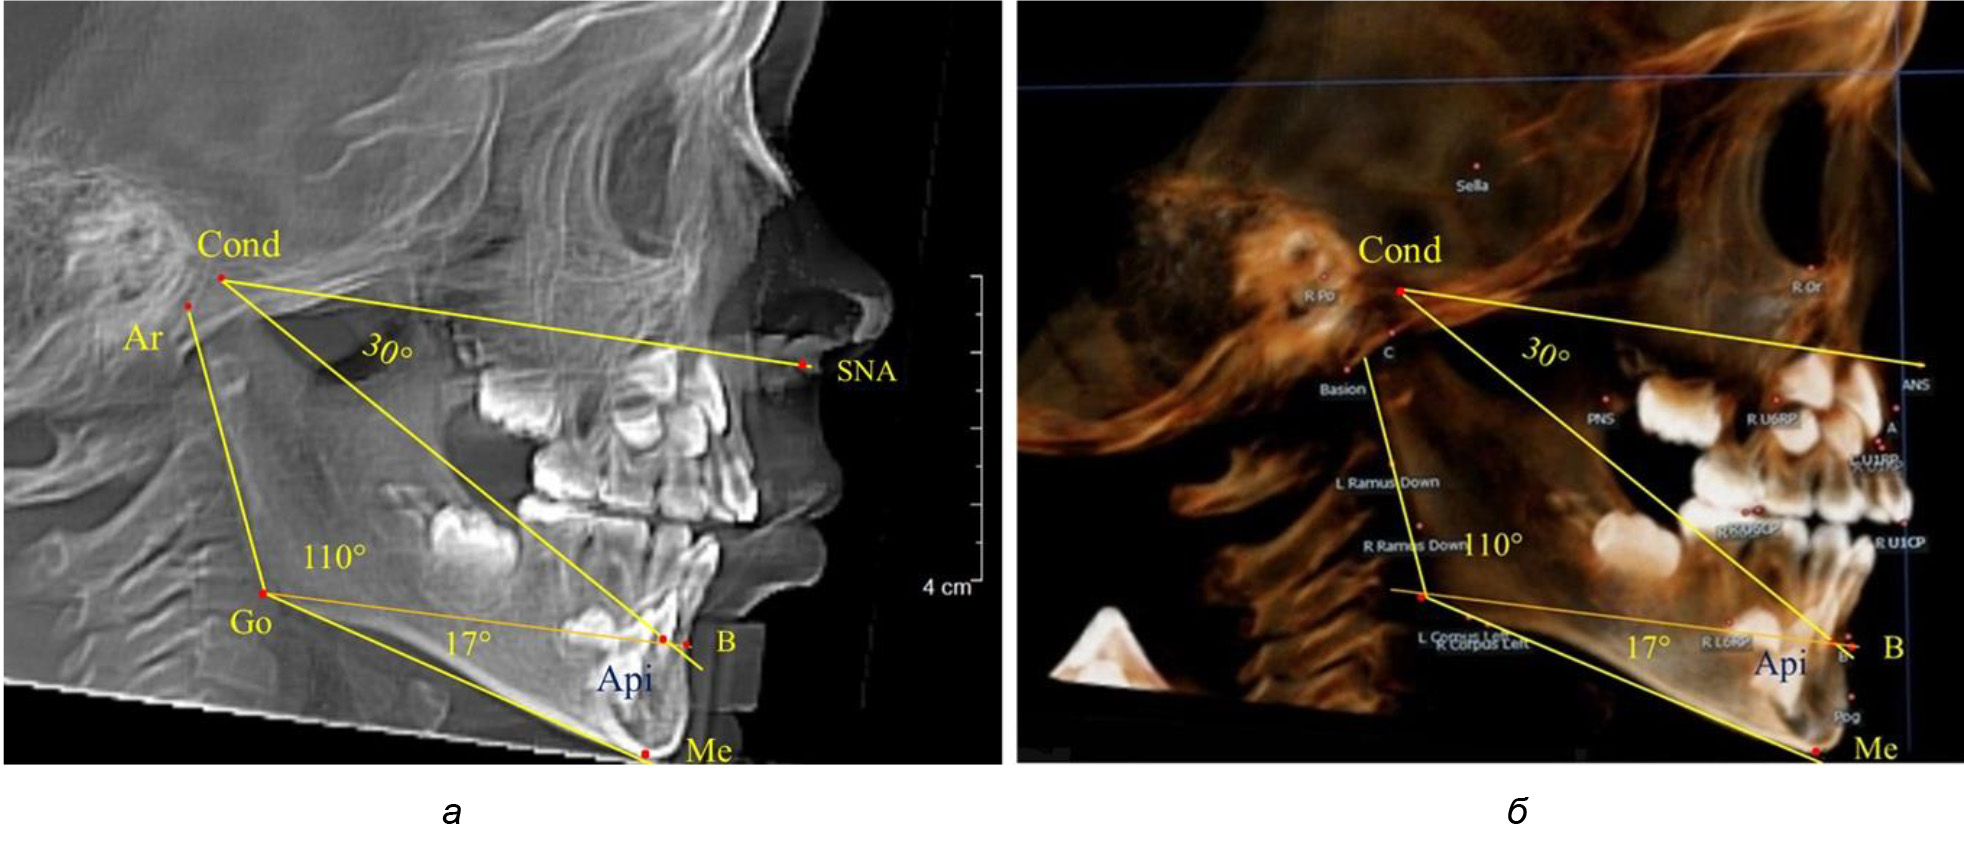

После смены всех молочных зубов (анализ 9 ТРГ) и после прорезывания вторых постоянных моляров (7 человек) происходил очередной этап подъема высоты прикуса с увеличением размеров костей гнатической части лица. Однако величина основного угла гнатической части лица SNA-Cond-Api, так же как в молочном и сменном прикусе, в норме составляла (30,02 ± 1,25)°, что не имело достоверных различий (р ˃ 0,05) с аналогичным параметром, анализируемом в других группах исследования. Угол нижней челюсти и его составляющие отличались вариабельностью параметров при различных показателях нижнечелюстного угла (рис. 6).

Рис. 6. Варианты 3D рентгенограмм детей после смены всех молочных зубов (а) и после прорезывания вторых моляров (б)

Таким образом, данные, полученные при исследовании детей с физиологическим прикусом в различные периоды онтогенеза, показали, что величина основного угла гнатической части лица SNA-Cond-Api была относительно стабильным параметром, вне зависимости от линейных параметров челюстных костей. Данный показатель может служить ориентиром для дифференциальной диагностики зубоальвеолярных и гнатических форм аномалий окклюзии в вертикальном направлении.